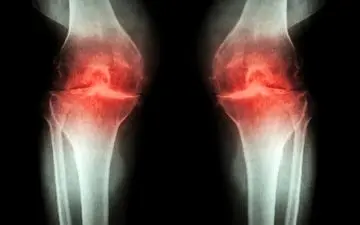

نقرس (Gout) نوعی آرتروز مفاصل است که در زمان بالا رفتن ماده شیمیایی اسید اوریک در خون، باعث جمع شدن بلورهای اسید…

تخریب مفصل، غضروف مفصلی است که در ادامه باعث می شود بافت استخوانی شروع به ساییده شدن کند ومفاصل سفت و دردناک می شود.

تاکنون دارویی برای درمان قطعی آرتروز مفاصل زانو کشف نشده و داروها معمولا نقش کاهنده درد را دارند.